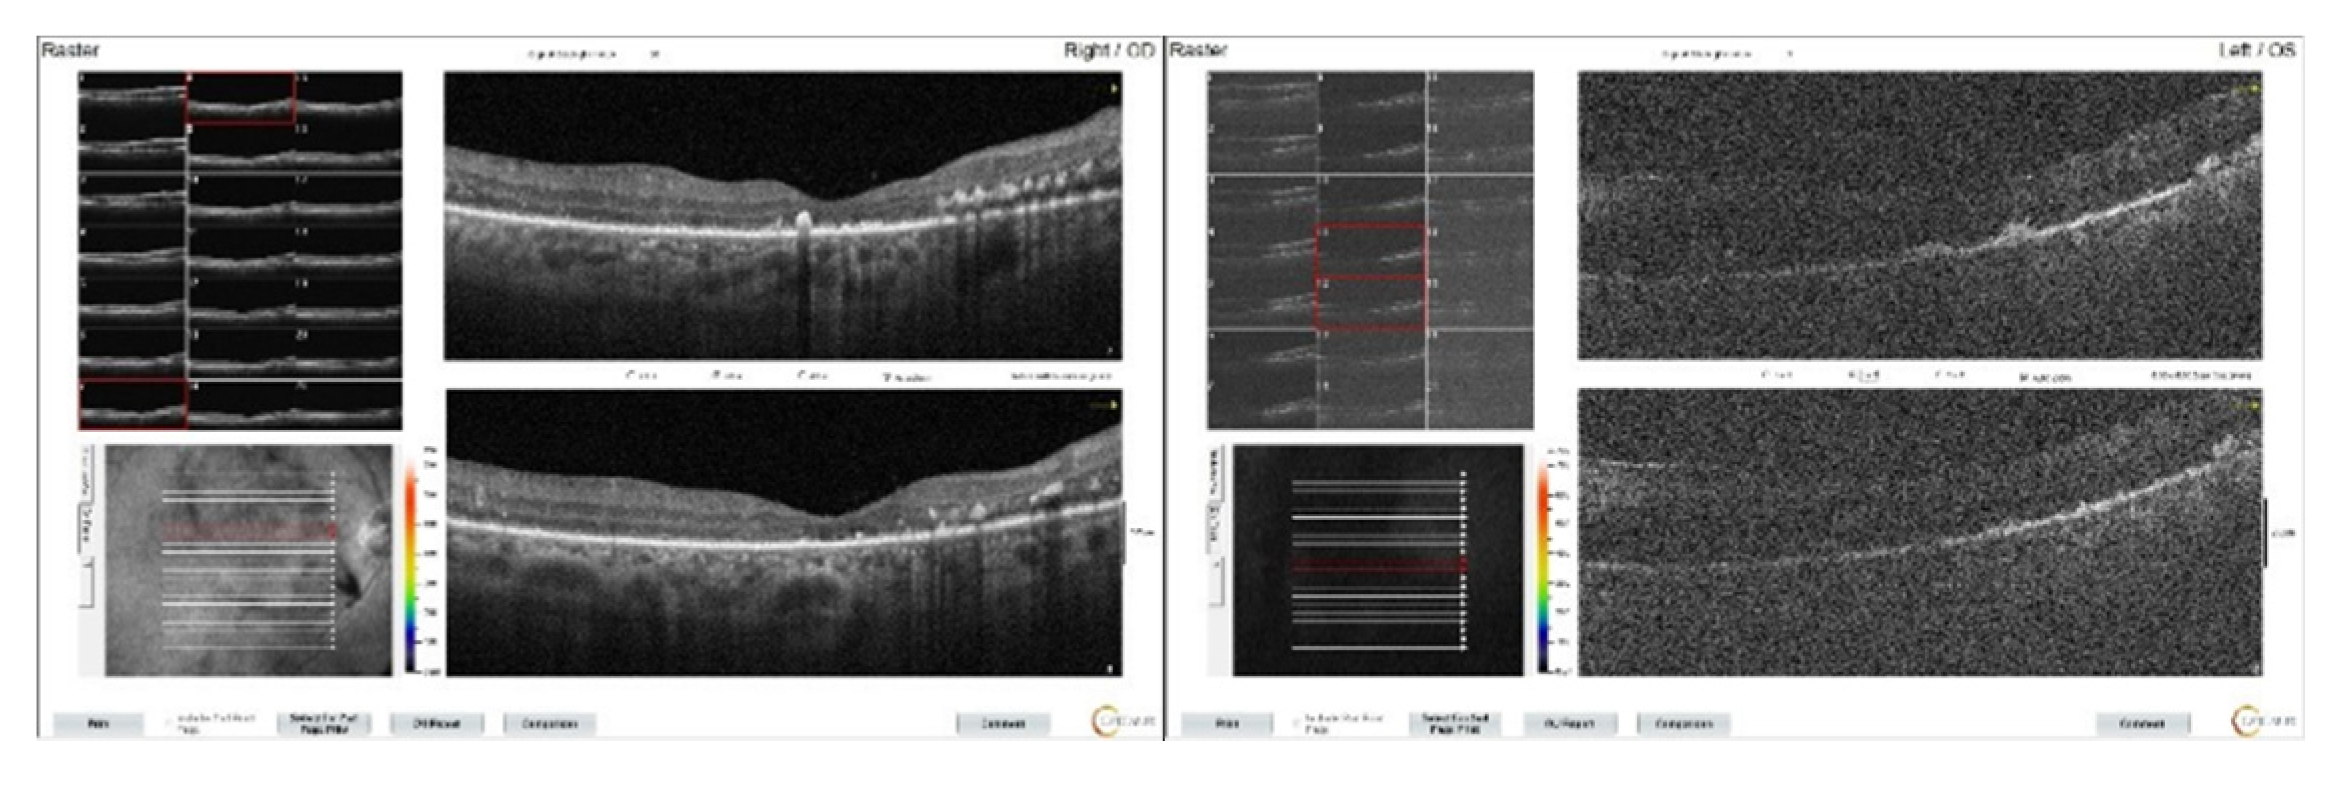

At the patient's first week follow-up after phacoemusification surgery, BCVA of the left eye did not increase and intraretinal fluid and subretinal dense serous fluid accumulation were detected on macular OCT (Figure 6). At that time, the patient's hemoglobulinA1c was 12.1 % (normal range: 3.5-6.7 %), and hemoglobin level was 13.6 g/dl (normal range:12.6- 17.4 g/dl) and due to DME, the patient is given bilateral monthly bevacizumab injections of 3 doses with a recommendation for diabetes regulation. However, it was observed that the patient’s macular edema does not regress, on the contrary, it increased (Figure 7). Subsequently, the patient was unable to attend the follow-ups for approximately one year. Upon returning one year later, ophthalmological examination revealed a BCVA of 20/200 in the right eye and finger counting at 2 meters in the left one. Bilateral pseudophakia with mild posterior subcapsular opacification in the left and no signs of rubeosis iridis was observed on biomicroscopy. IOPs in both eyes were within normal limits (16/16 mmHg). Fundus examination of the right eye revealed extensive retinal hemorrhages, hard exudates, microaneurysms, with subretinal and intraretinal edema in the macula. The left eye could not be visualized, and its ultrasonography was consistent with intravitreal hemorrhage. Upon inquiring about the systemic condition of the patient, it was learned that approximately one month ago, he was diagnosed with MM and chemotherapy had started. The patient was advised to remain in a sitting position and continuation of the systemic treatment was recommended. At that time, the patients hemoglobin level was 11.7 g/dL (normal range:13.2 - 16.6 g/dL), and hemoglobin A1c was 6.7% (normal range:3.5 - 5.7%).

Figure 6. Bilateral macular OCT images of the patient at the first week after left cataract surgery. While mild macular edema continues on the right, numerous intraretinal cysts accompany dense subretinal serous fluid on the left.

Figure 7. Macular OCT images of the patient after 3 monthly intravitreal bevacizumab injections. Subretinal serous fluid accumulation is clearly visible in both maculas.